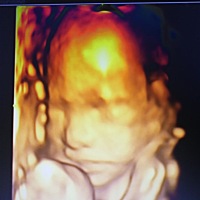

发现怀孕多久去照B超